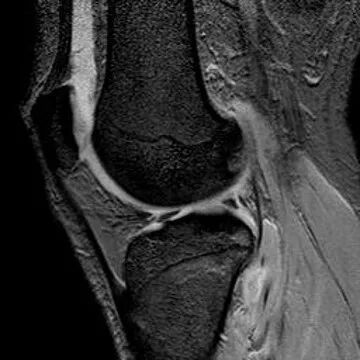

半月板水平撕裂

1、水平撕裂

2、较少见3、III级高信号与胫骨平台平行,到达半月板的游离缘或一侧关节面

(半月板水平撕裂)